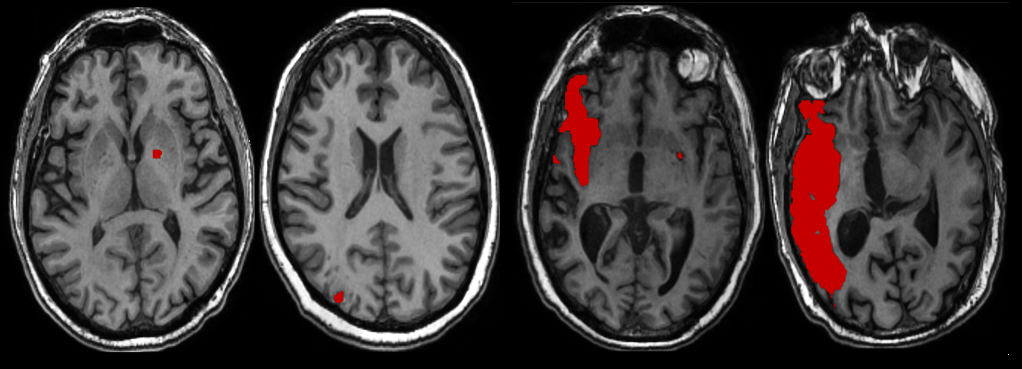

Refer to caption

Figure 2: Diverse representations of stroke (in red) in MRI scans.

Identifying and segmenting stroke lesions from MRI is a critical aspect of selecting the right clinical interventions and formulate an accurate forecast about the patient’s recovery [18]. Figure 2 shows diverse types of strokes in different sizes and locations, making it difficult to accurately identify and delineate these pathologic phenomena. However, despite these technological advancements, current models still have challenges in accurately detecting stroke lesions of varying sizes within unified diagnostic framework [19].